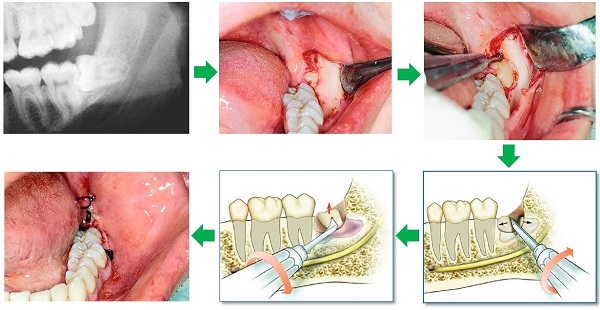

- Bước 3: Nhổ răng

Bác sĩ tiến hành nhổ răng bằng công cụ y tế chuyên khoa. Có thể nhổ toàn bộ răng hoặc cần cắt nhỏ răng và lấy ra từng phần. Vì nhiều trường hợp, răng khôn có thể có chân răng cong, to hoặc nằm sâu nên rất khó lấy ra nguyên vẹn. Bác sĩ sẽ dùng máy khoan chia răng thành 2–3 phần nhỏ, sau đó dùng kẹp nha khoa lấy ra từng mảnh.

- Bước 4: Cầm máu và khâu vết thương

Bác sĩ vệ sinh hốc răng sạch sẽ để loại bỏ mảnh vụn xương, răng, tránh nhiễm trùng. Vết mổ được khâu lại bằng chỉ tự tiêu (thường là loại tan sau 7–10 ngày), không cần cắt chỉ.